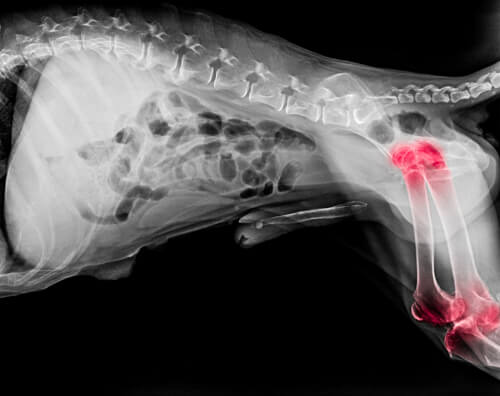

Exceso de vitamina A

El consumo de esta vitamina en grandes cantidades puede conducir a la toxicidad de la vitamina A o hipervitaminosis A. La toxicidad podría generar problemas óseos, similares a la artritis. Nunca alimentes a tu perro con hígado si también está tomando suplementos de vitamina A.

Las purinas son sustancias que el cuerpo convierte en ácido úrico. Si existe una condición renal que impida la expulsión del ácido úrico a través de los riñones, puede acumularse en el torrente sanguíneo y depositarse como cristales en forma de aguja en las articulaciones.

Estos cristales son la causa de la inflamación severa y el dolor intenso asociado al ácido úrico. Este tema es particularmente importante en perros propensos a hacer cálculos de ácido úrico, especialmente común en la raza dálmata y bulldog inglés.